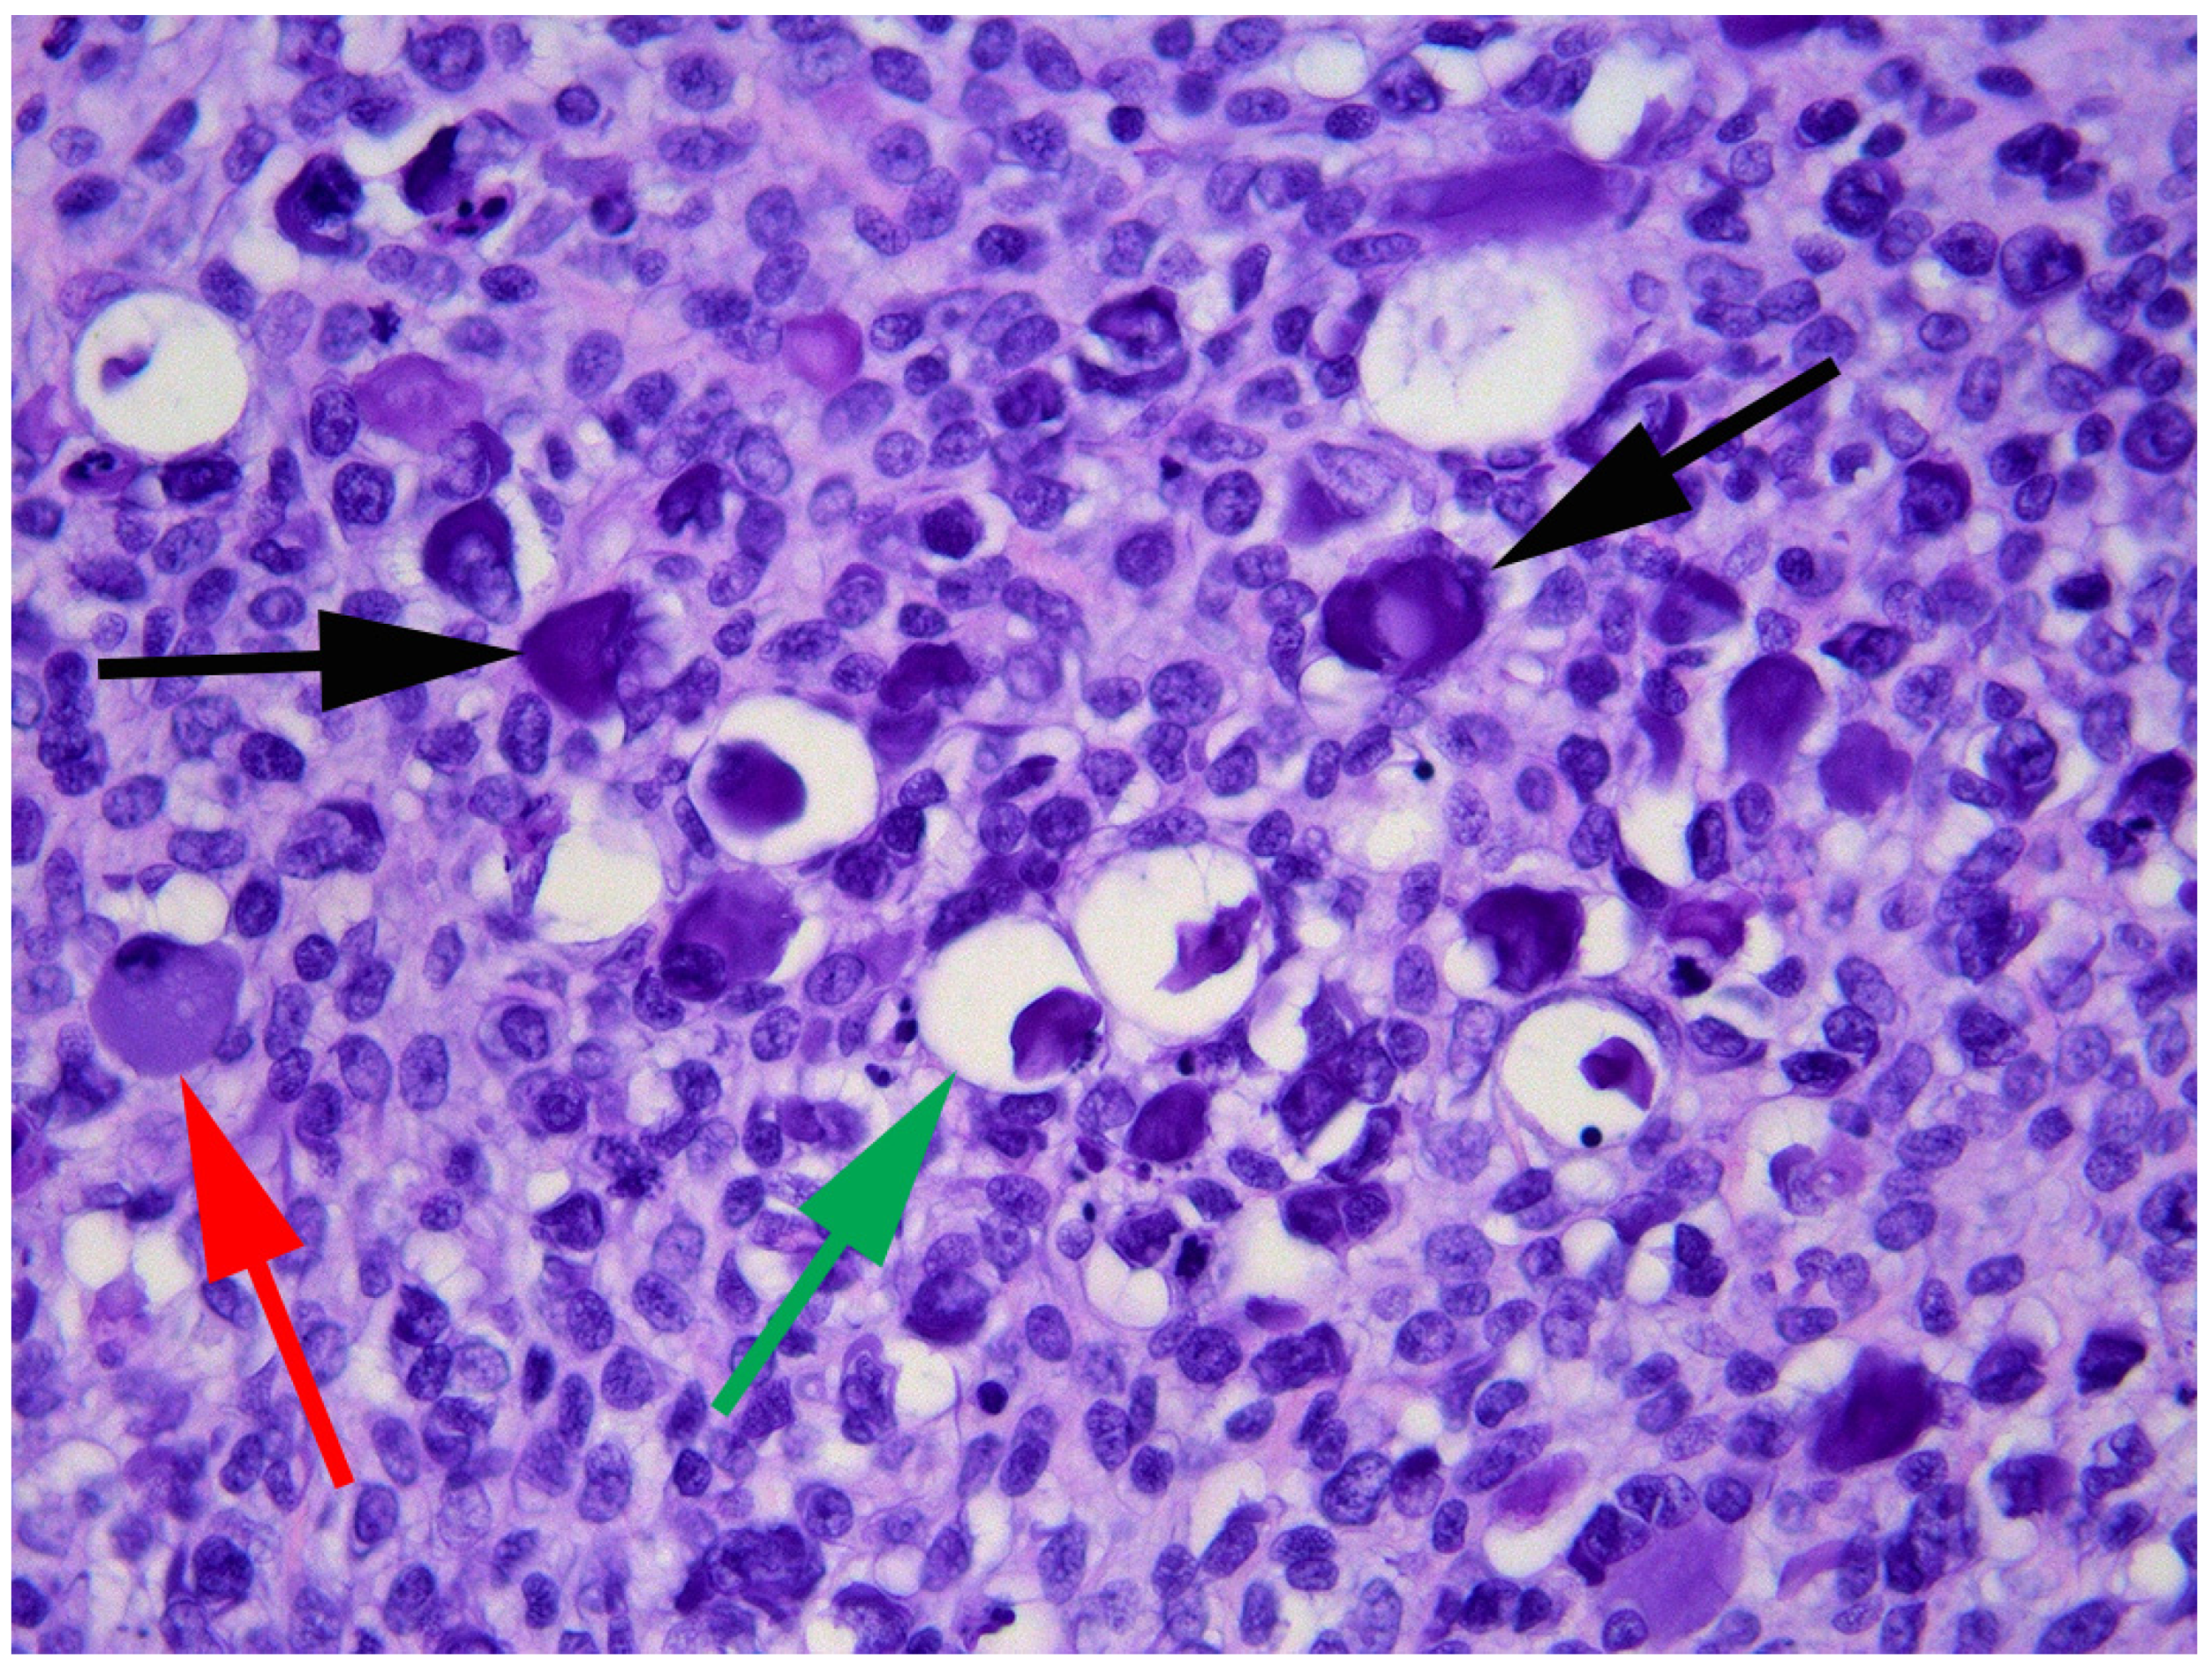

2. Case Presentation and Diagnosis